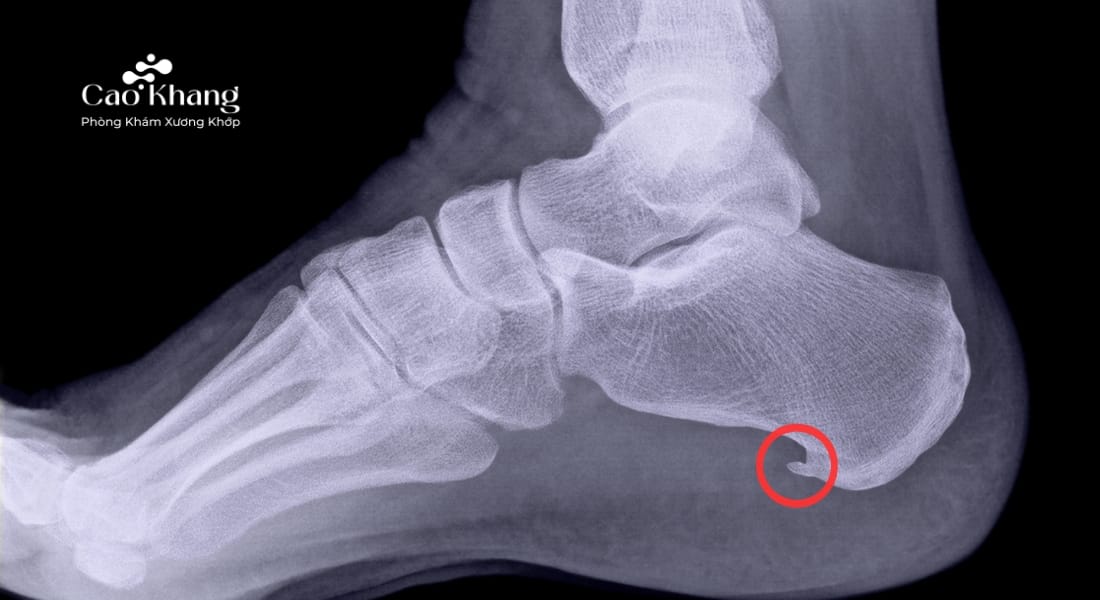

Gai gót chân (hay còn gọi là “gai xương gót”, “calcaneal spur”) là hiện tượng hình thành một mỏm xương nhỏ nhô ra ở mặt dưới xương gót. Mỏm xương này có thể dài từ vài mm đến hơn 1cm, thường có hình dạng giống cái gai nhọn trên phim X-quang. Gai gót chân không phải là một khối u, cũng không phải tổn thương ác tính, mà là hậu quả của quá trình lắng đọng canxi ở vị trí cân gan chân bám vào xương gót.